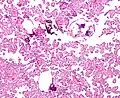

The tumor is neuroectodermal in origin and similar in structure to a normal choroid plexus. They may be created by epithelial cells of the choroid plexus. Papillary fronds lined by bland columnar epithelium are visible under the microscope. Normal absences include mitotic activity, nuclear pleomorphism, and necrosis.[10] Tumors have positive immunohistochemistry for cytokeratin, vimentin, podoplanin, and S-100.[11] Up to 20% of choroid plexus papilloma patients may test positive for glial fibrillary acidic protein (GFAP).[12] Studies have found that fourth ventricle cancers express more S100 than lateral ventricle tumors, and older patients (over 20 years) express more GFAP and transthyretin than younger patients.[13] Some individuals with choroid plexus papilloma have germline TP53 gene mutations, according to genetic analyses.[14] These cancers rarely exhibit nuclear p53 protein positivity. Aicardi syndrome, hypomelanosis of Ito, and 9p duplication are syndromic correlations of choroid plexus papilloma.

Plexuspapillom Overview